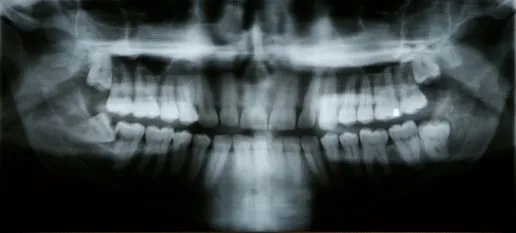

A tooth becomes impacted when there is not enough room to accommodate the space in the dental arch and growth becomes impossible. After surgery to remove an impacted tooth, mild discomfort and some swelling is expected. This is part of the process and should not alarm you. You may use cold compresses to alleviate the swelling. In addition, your doctor may prescribe pain medication, which should be taken as directed. Patients are also advised to favor the extraction area and modify their diet for a few days to allow for healing.